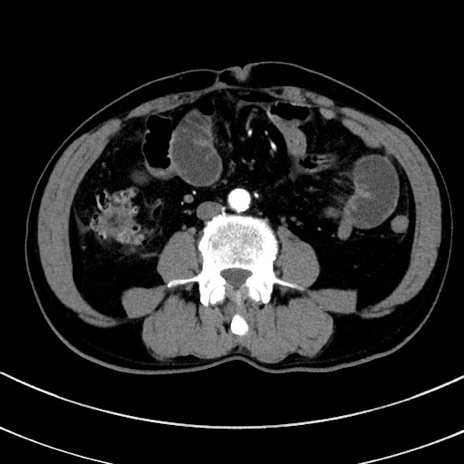

症例8(横断像)

【症例】 60歳代男性

【主訴】 黒色吐物

【現病歴】 4日前から嘔気自覚、2日前の朝食後にも嘔気あり、自分で手で嘔吐反射起こし嘔吐したところ血が混ざっていたため受診。

【既往歴】 5年前汎発性腹膜炎を伴う急性虫垂炎で手術、高血圧、前立腺肥大症、高脂血症

【身体所見】 腹部正中に手術癩痕あり 腹部平坦・軟圧痛なし膨満感あり

【データ】WBC 8400、CRP 4.54